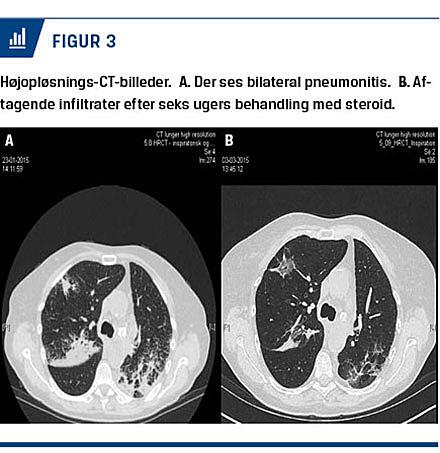

Pneumonitis, der er en inflammatorisk tilstand i lungeparenkymet, kan vise sig i form af hoste, åndenød, brystsmerter og feber.

Ved nytilkomne eller forværrede pulmonale symptomer udredes patienterne for ikkeimmunrelaterede årsager og behandles relevant hvis dette påvises. Der skal laves udvidet lungefunktionsundersøgelse og CT

af thorax (Figur 3). Overvej antibiotisk behandling ved den mindste mistanke om infektiøs årsag.